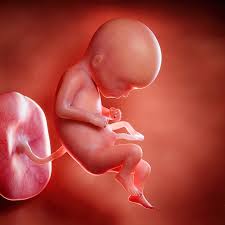

So gibt es eineiige und zweieiige Zwillinge. Im Moment ist es rund 37 Zentimeter groß und etwa 1300 Gramm schwer. Entwicklung des Körpers Ab dieser Schwangerschaftswoche wird es etwas unspektakulärer.

Schwangerschaftswoche schreitet auch die Entwicklung Deines Kindes weiter voran. SSW Entwicklung des Körpers Ultraschall. Heutzutage können die Ärzte Frühchen ab der 24. Zwillinge in der 9. Das Gehirn Deines Kindes wächst in der 29. Hier kannst du nachlesen wie die Entwicklung von Zwillingen während der Schwangerschaft vonstatten geht. Im Moment ist es rund 37 Zentimeter groß und etwa 1300 Gramm schwer.